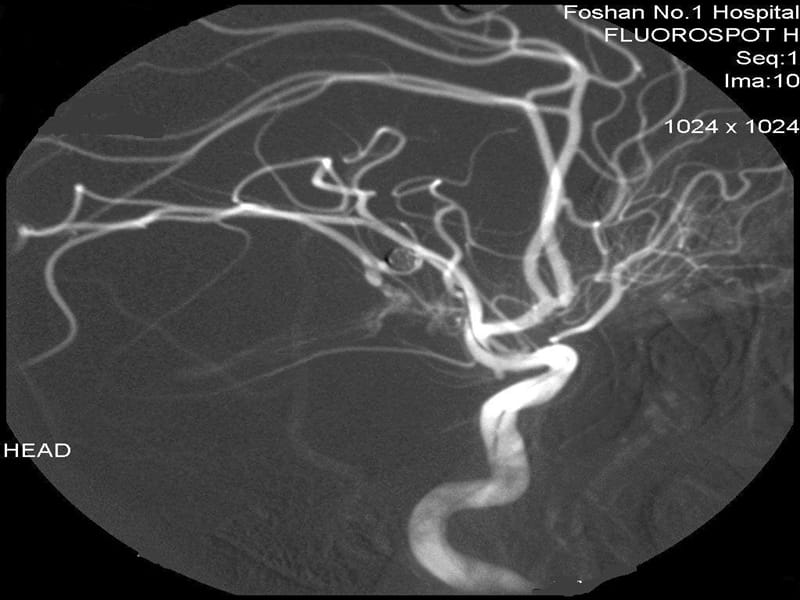

编辑功能性神经影像学的常用方法包括

- 正电子发射断层扫描 (PET)

- 功能磁共振成像 (fMRI)

- 脑电图 (EEG)

- 脑磁图 (MEG)

- 功能性近红外光谱 (fNIRS)

- 单光子发射计算机断层扫描 (SPECT)

- 功能性超声成像 (fUS)

PET、fMRI、fNIRS 和 fUS 可以测量与神经活动相关的脑血流局部变化。 这些变化被称为激活。 当受试者执行特定任务时被激活的大脑区域可能在有助于行为的神经计算中发挥作用。 例如,枕叶的广泛激活通常出现在涉及视觉刺激的任务中(与不涉及视觉刺激的任务相比)。 大脑的这一部分接收来自视网膜的信号,并被认为在视觉感知中发挥作用。